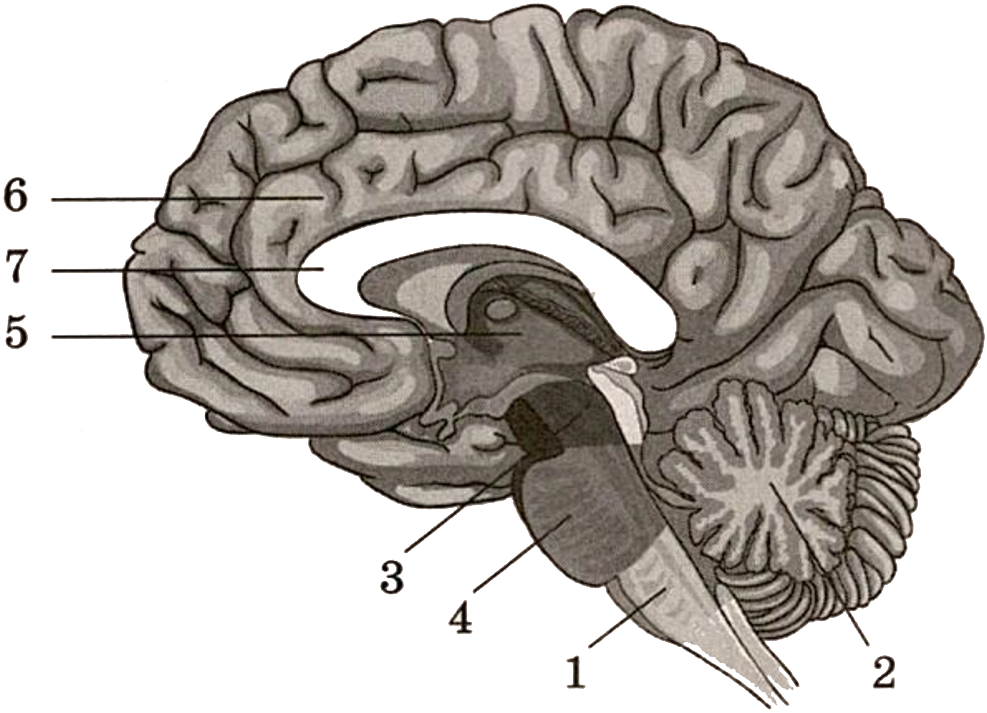

Анатомические снимки верхнелатеральной поверхности головного мозга